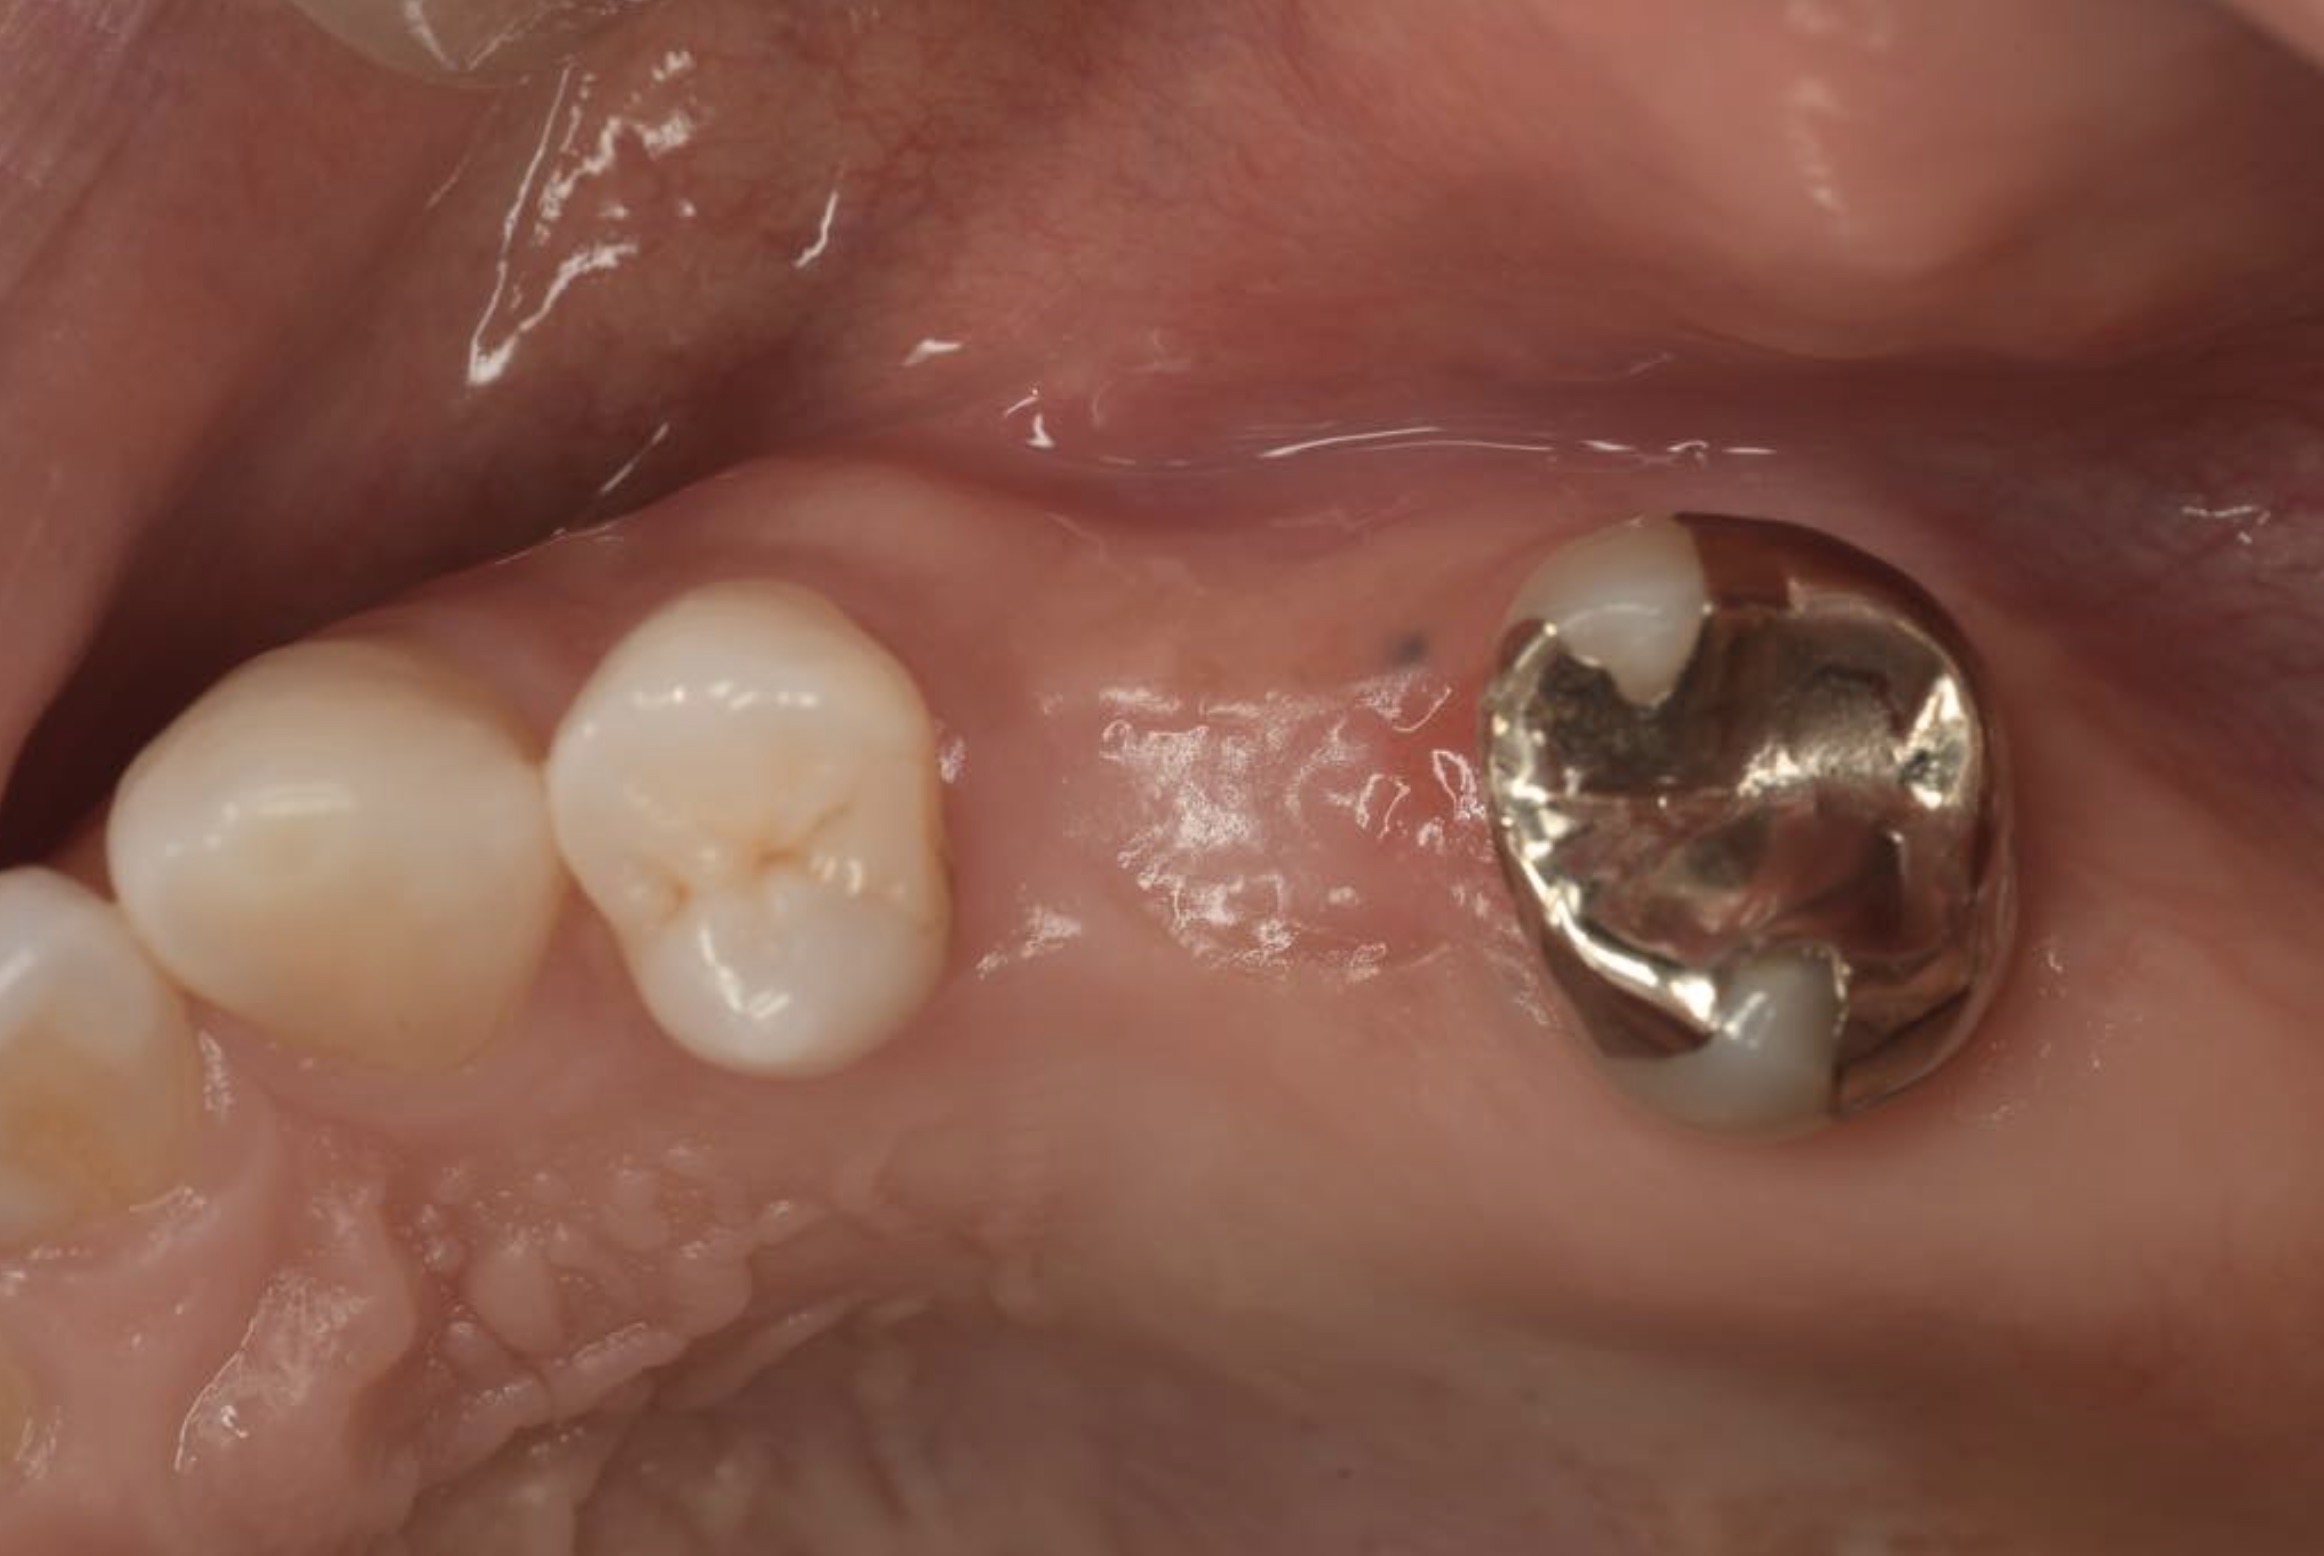

CASE 01

| 主訴 | 歯が割れた |

| 治療内容 | 左下6番 インプラント治療(骨の再生療法含む) |

| 治療回数 | 14回 |

| 治療費用 | ¥460,000 |

| 想定される副作用 | 腫れ、痛み |